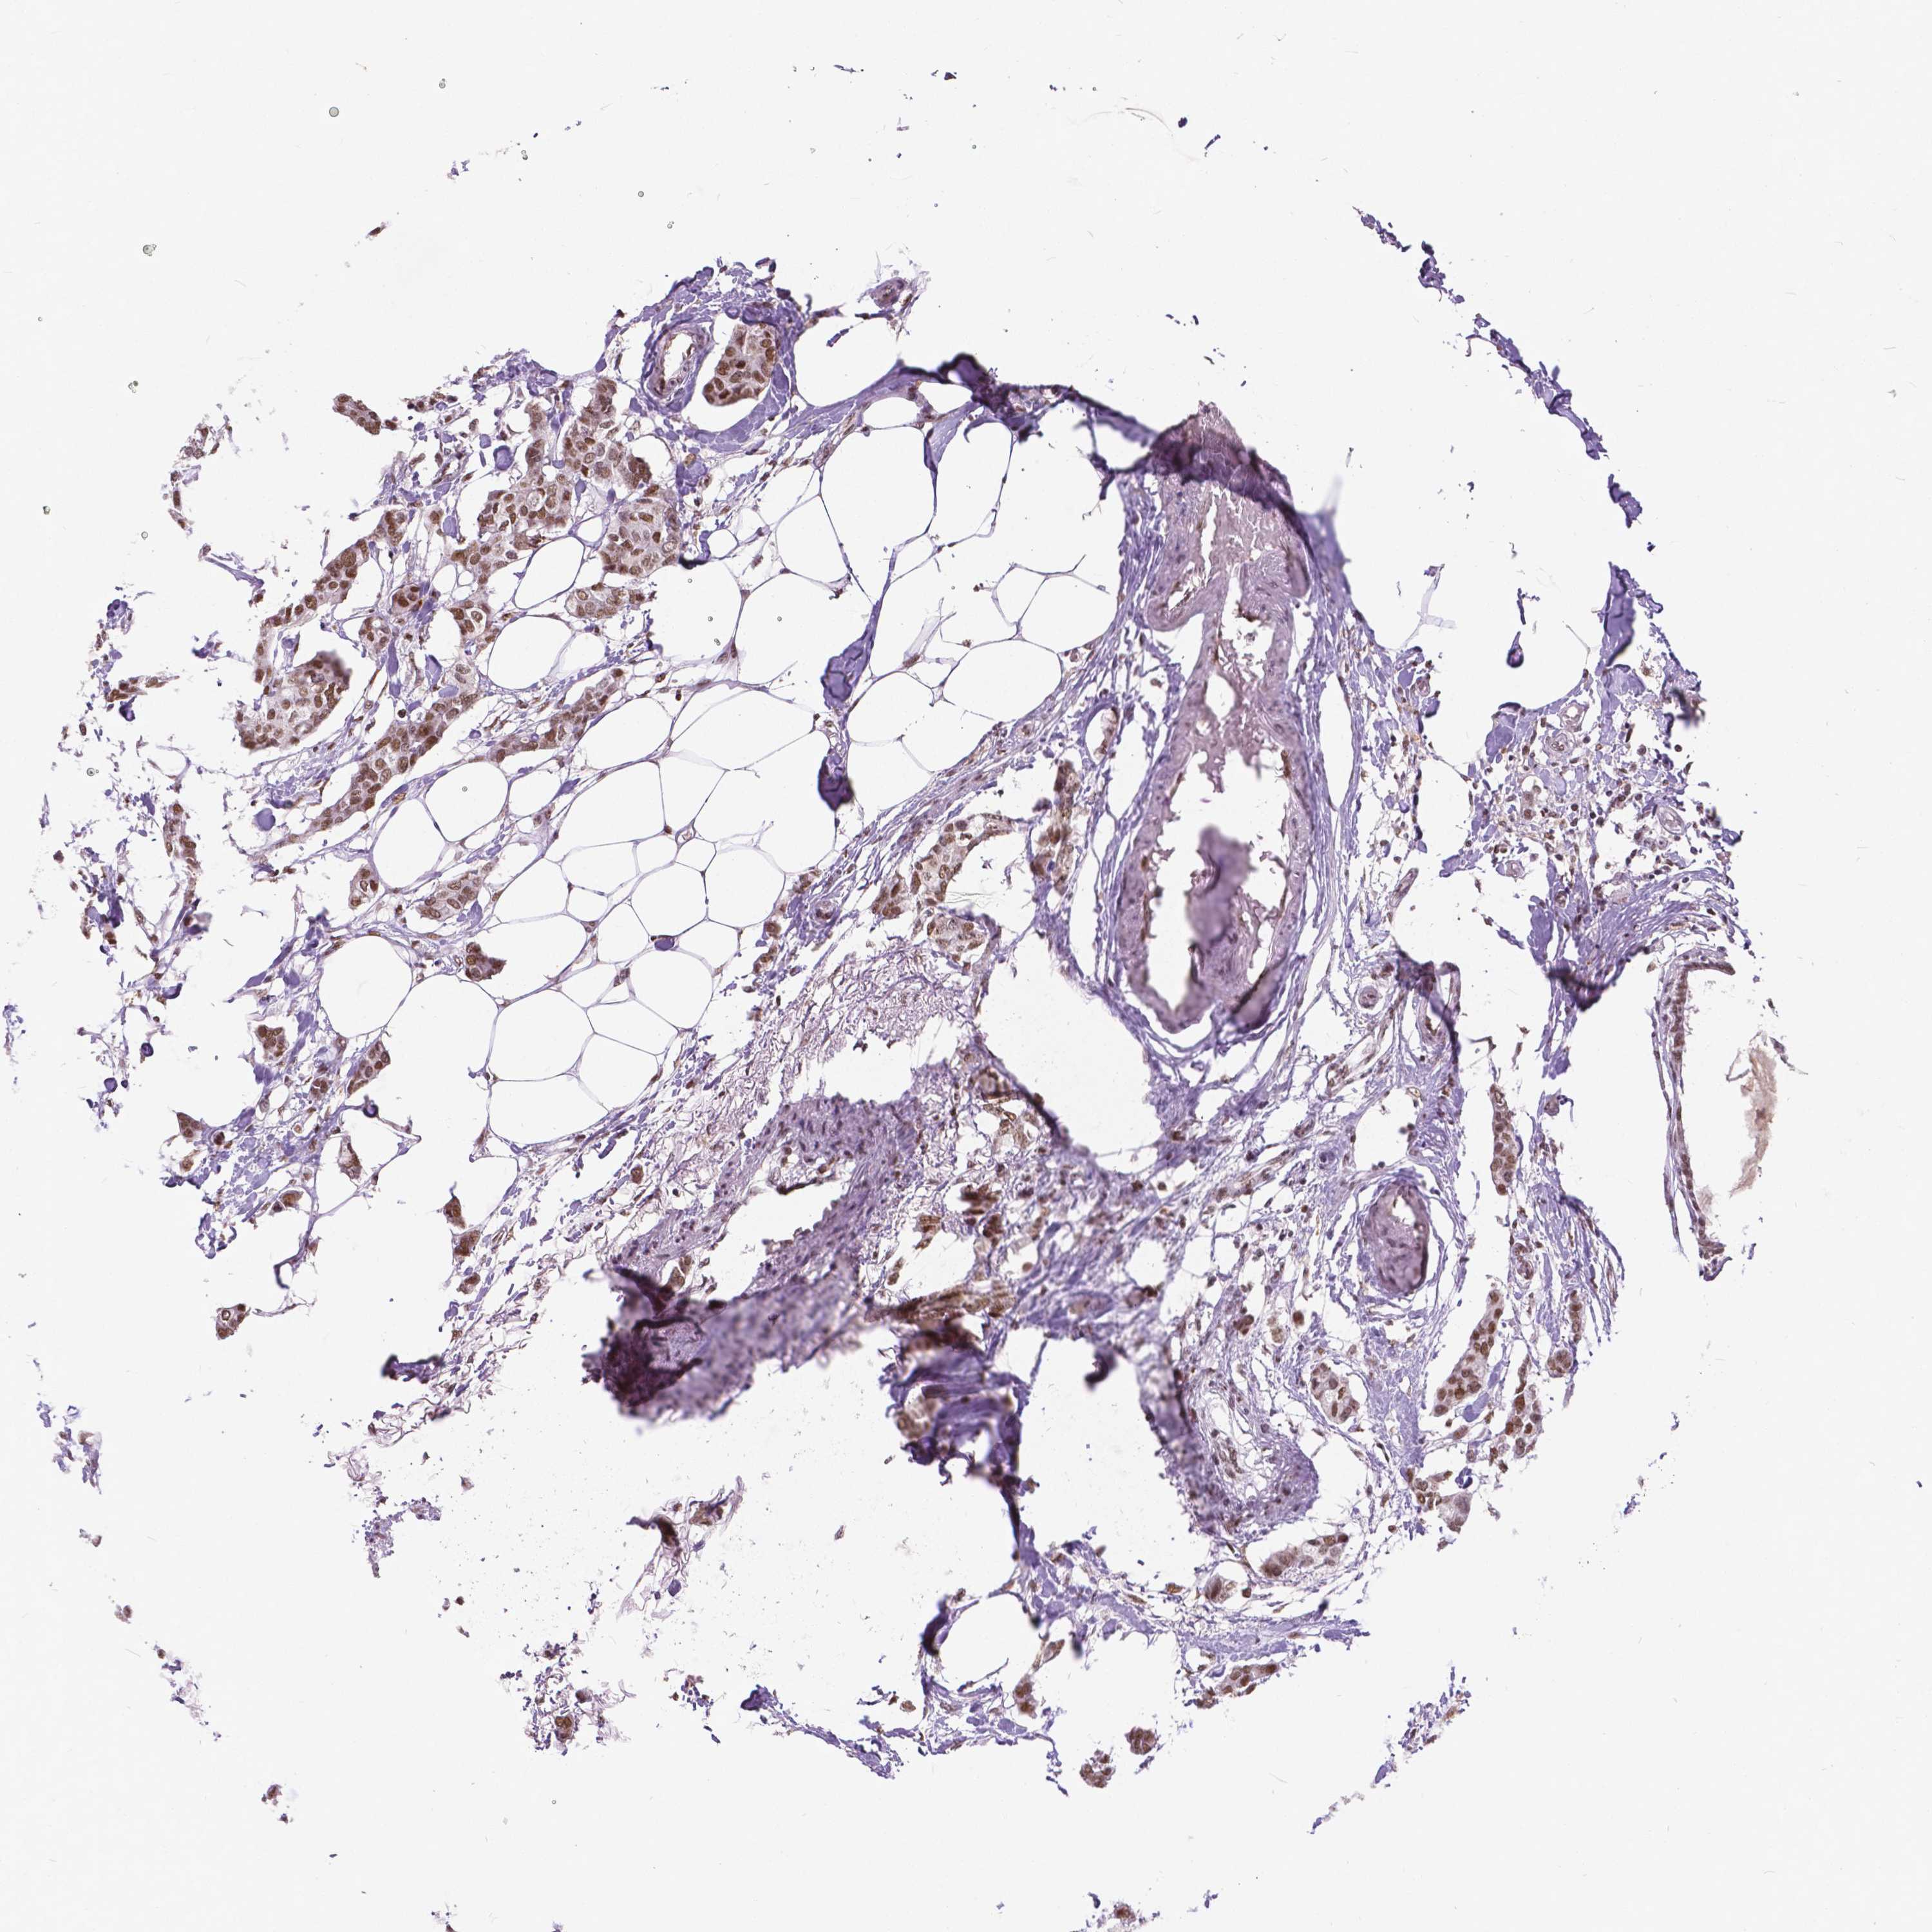

CANCER BREAST CANCER Show tissue menu

BRCA TCGA BRCA VALIDATION PROTEIN EXPRESSION